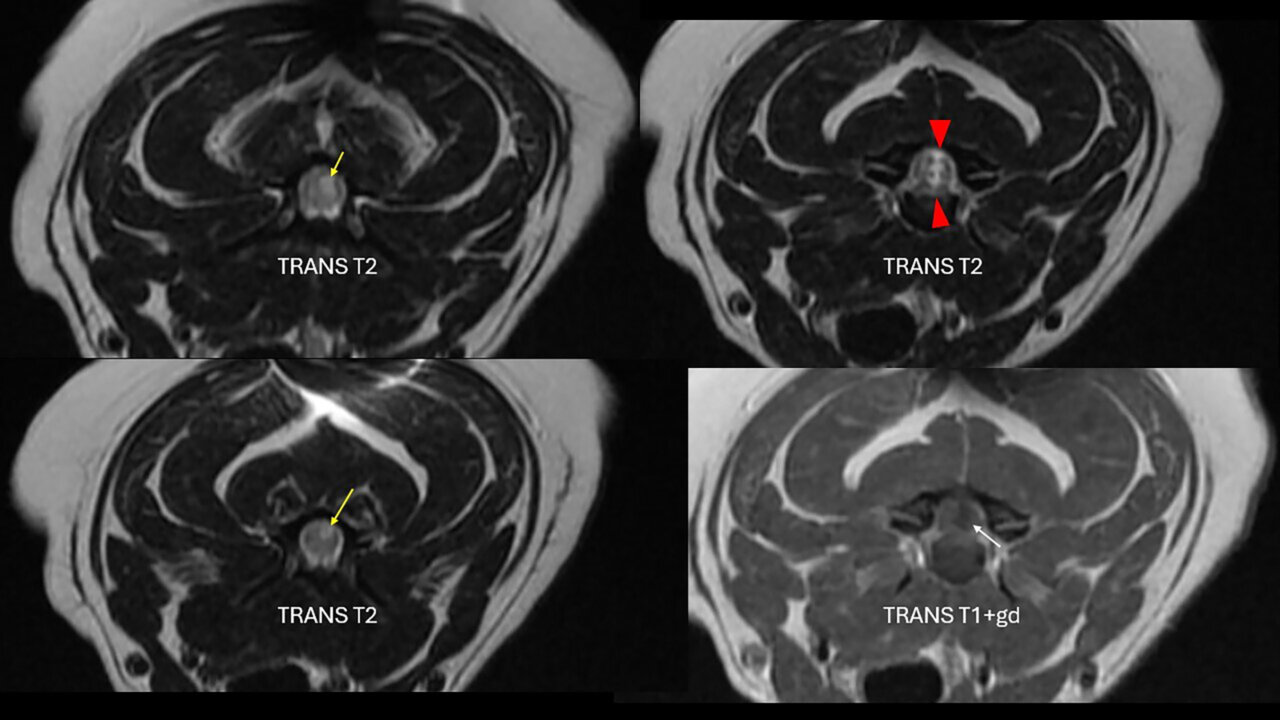

Se hospitalizó para realizar el protocolo diagnóstico con RM de los segmentos medulares comprendidos entre C1-T2. El estudio mediante RM (1,5 T) de la columna cervical se realizó incluyendo las siguientes secuencias: sagitales (T2w, 3D T2, STIR, T1w, T1w+Gd); transversales (T1w, T2w, T1w+Gd); dorsales (FIESTA, 3D). Se observó una pérdida de volumen del disco C3-C4 que mantenía una señal correcta en T2w. Justo dorsal al disco y, a nivel intramedular, se apreció una marcada lesión lineal hiperintensa en T2w y STIR e hipointensa en T1w que atravesaba la médula espinal en sentido dorsoventral, ligeramente lateralizada a la derecha. Tanto craneal como caudal a dicha lesión, hasta la mitad caudal de C3 y a la mitad craneal de C4, se vio una señal intramedular, hiperintensa en T2w y STIR, pero más difusa, también lateralizada a la derecha y dorsal. Este estudio no mostró evidencia de material extradural que causara compresión medular (imágenes 3A y 3B).

Imagen 3. Caso 2. A) RM, cortes sagitales utilizando distintos tipos de secuencias. Se aprecia un trayecto en dirección dorsal desde el espacio IV C3-C4 hasta el parénquima medular (flechas amarillas; sag 3D T2 cube) que muestra señal hiperintensa craneal y caudalmente a dicho espacio (flecha roja; sag T2). El disco C3-C4 muestra un menor volumen (puntas de flecha azules; sag STIR) y no se evidencia la presencia de material degenerado compresivo en el canal vertebral (sag T1+gd). Resonancia magnética informada por ProtonVet. B) RM, cortes transversales en T2 y T1 poscontraste. Se observan las zonas de hiperintensidad en T2 craneal y caudalmente (flechas amarillas) al trayecto que va en dirección ventro-dorsal (puntas de flecha rojas) que podrían ser compatibles con zonas de gliosis, edema o malacia. En T1, la zona justo dorsal al disco, se aprecia hipointensa (flecha blanca). Resonancia magnética informada por ProtonVet.